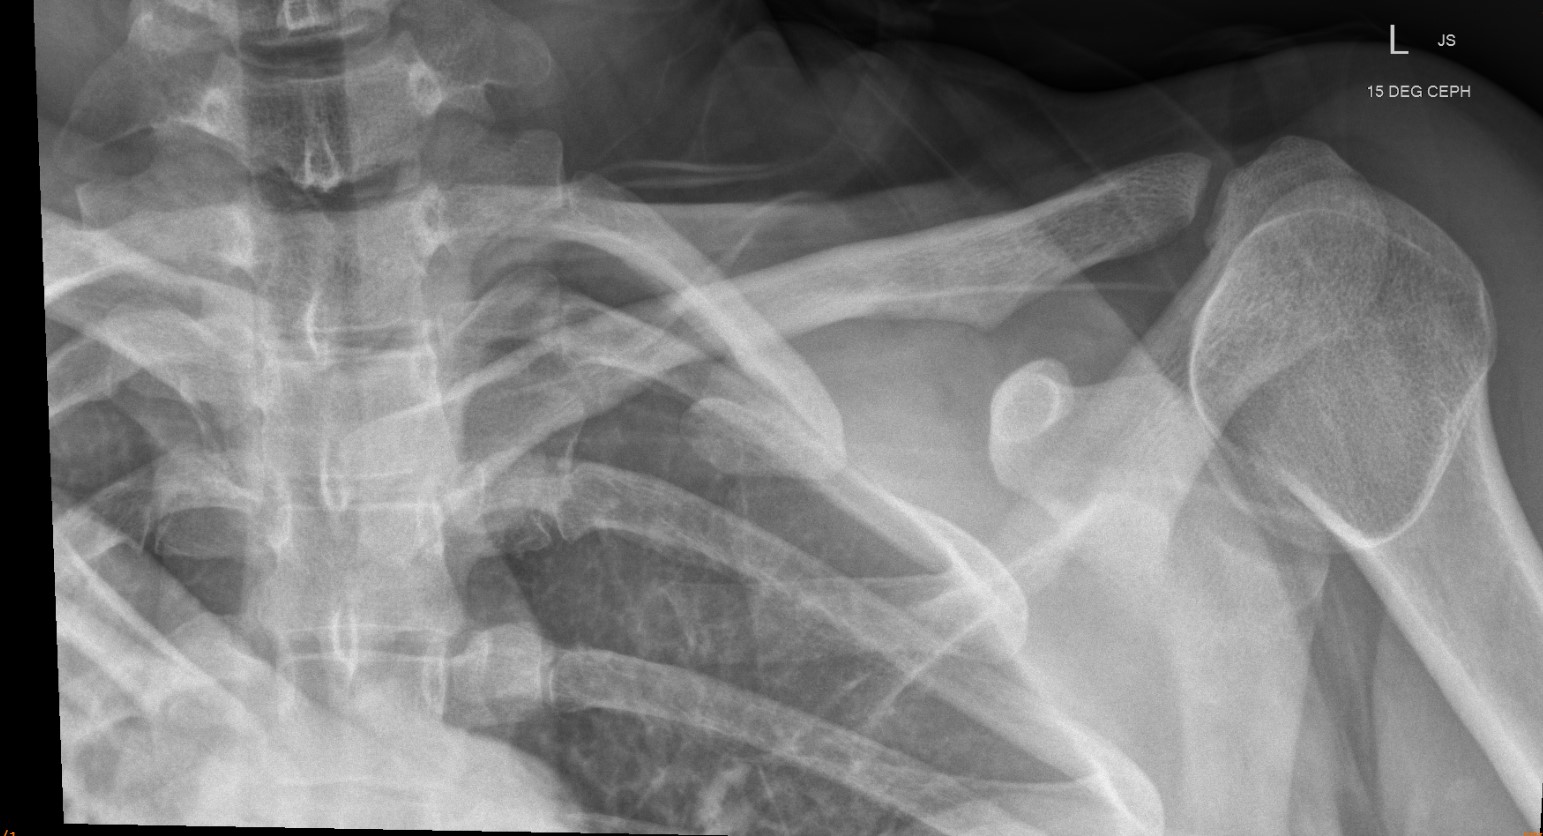

Xray

Can be missed on a xray

Left posterior SCJ dislocation with pre- and post angiogram

Severe left posterior SCJ dislocation with subclavian vein compression